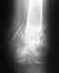

перелом позвоночника 12 грудной

у брата перелом позвоночника, 12 грудной,в рзультате падения с 6-метровой высоты до операции чувствовал обе ноги, после операции не чувствует одну ни как, другую чуть чуть, с операции прошла неделя, врач говорит начинать ходить, а как если ноги не чувствует?? помогите, скажите сколько восстанавливаться после такой операции